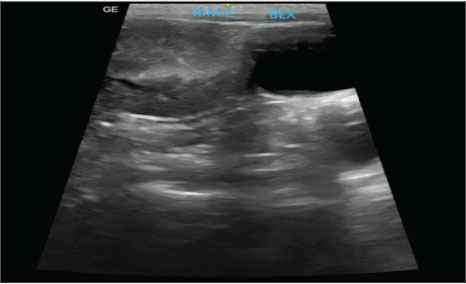

Abdominal ultrasound examination revealed the left kidney in an ectopic position in the left caudal region of the abdomen, adjacent to the bladder. The organ had irregular contours, measuring approximately 3.42 cm in length along the longitudinal axis, with moderate loss of internal structure and reduced corticomedullary differentiation, consistent with chronic nephropathy (Fig. 1). The right kidney was not identified, and the other abdominal organs were within normal limits. Ultrasound findings were consistent with left renal ectopia.

Fig. 1. Ultrasound image showing the left kidney in an ectopic position in the left caudal region of the abdomen, close to the bladder. The organ presented with irregular contours, moderate loss of internal structure, and reduced CM differentiation.